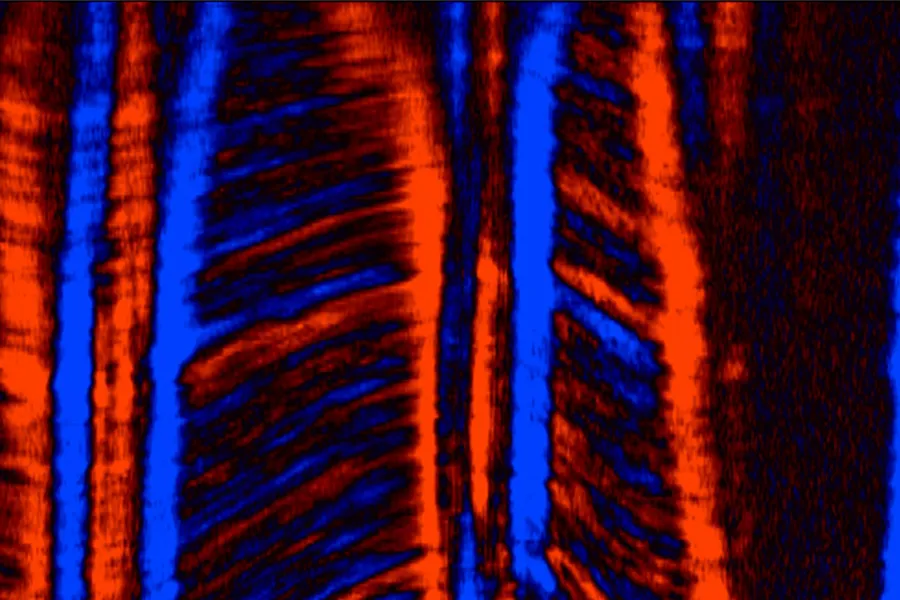

The research project focusses on novel imaging modalities for myocardial tissue characterisation by cardiac magnetic resonance imaging and high frame rate echocardiography. Remodelling of the myocardium and development of myocardial fibrosis is associated with cardiac dysfunction and severe arrhythmia. Enhanced imaging techniques for myocardial tissue characterisation may improve diagnostics and treatment across a broad spectrum of cardiac diseases.

The aims of the project are to fill existing research gaps regarding myocardial fibrosis in athletes and patients with cardiac diseases as well as to enhance non-invasive myocardial tissue characterisation by mechanical wave imaging using high frame rate echocardiography.